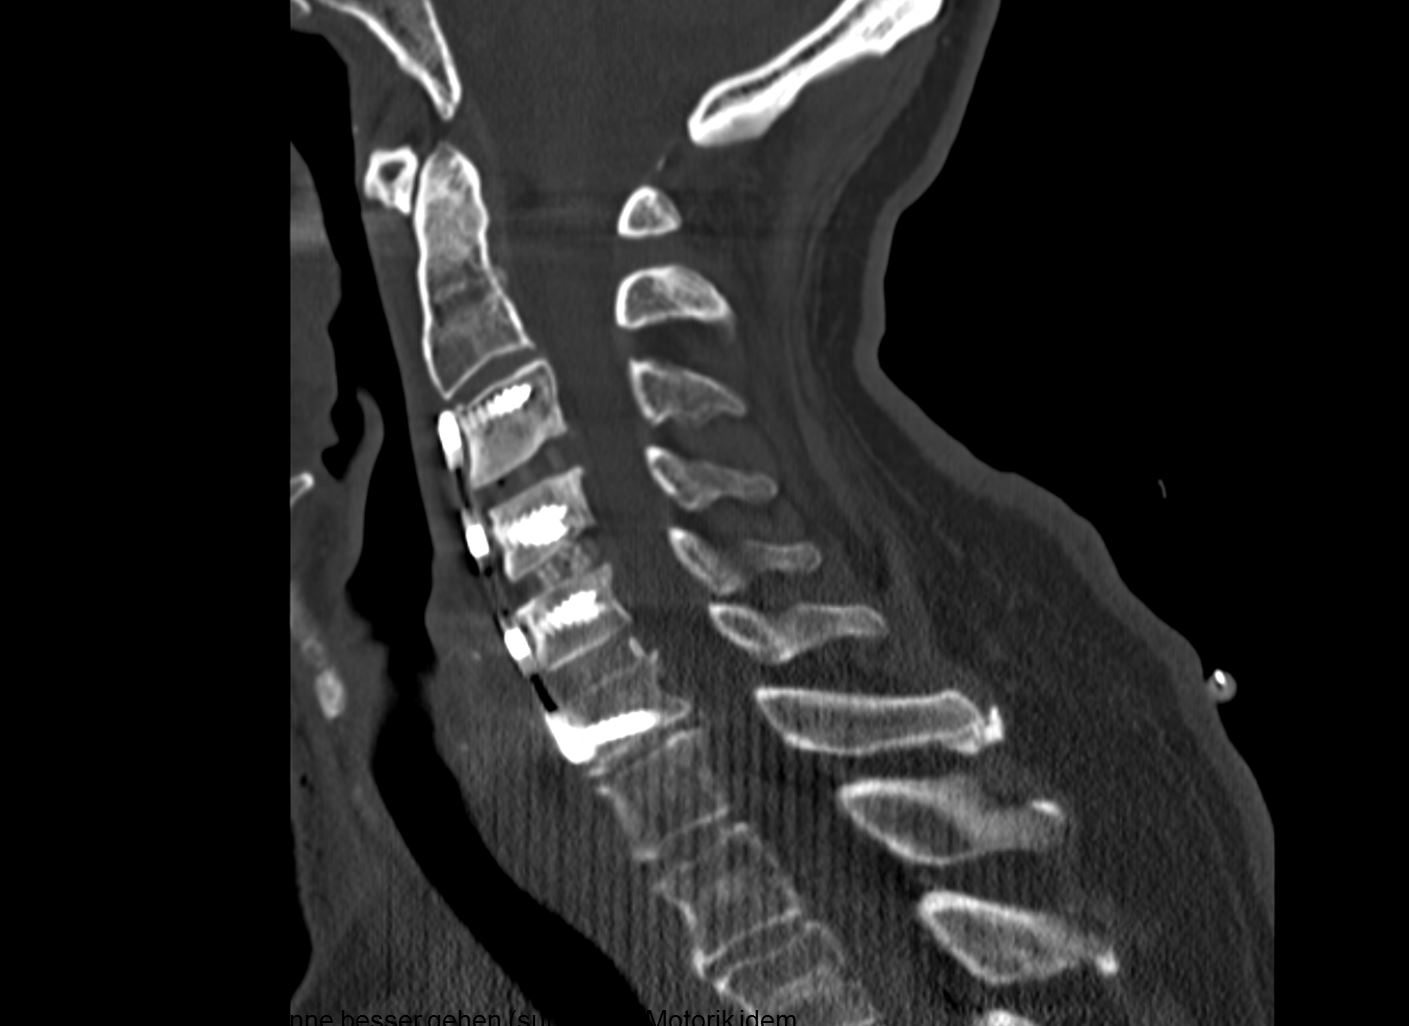

Αυχενική Δισκεκτομή σε 3 Επίπεδα